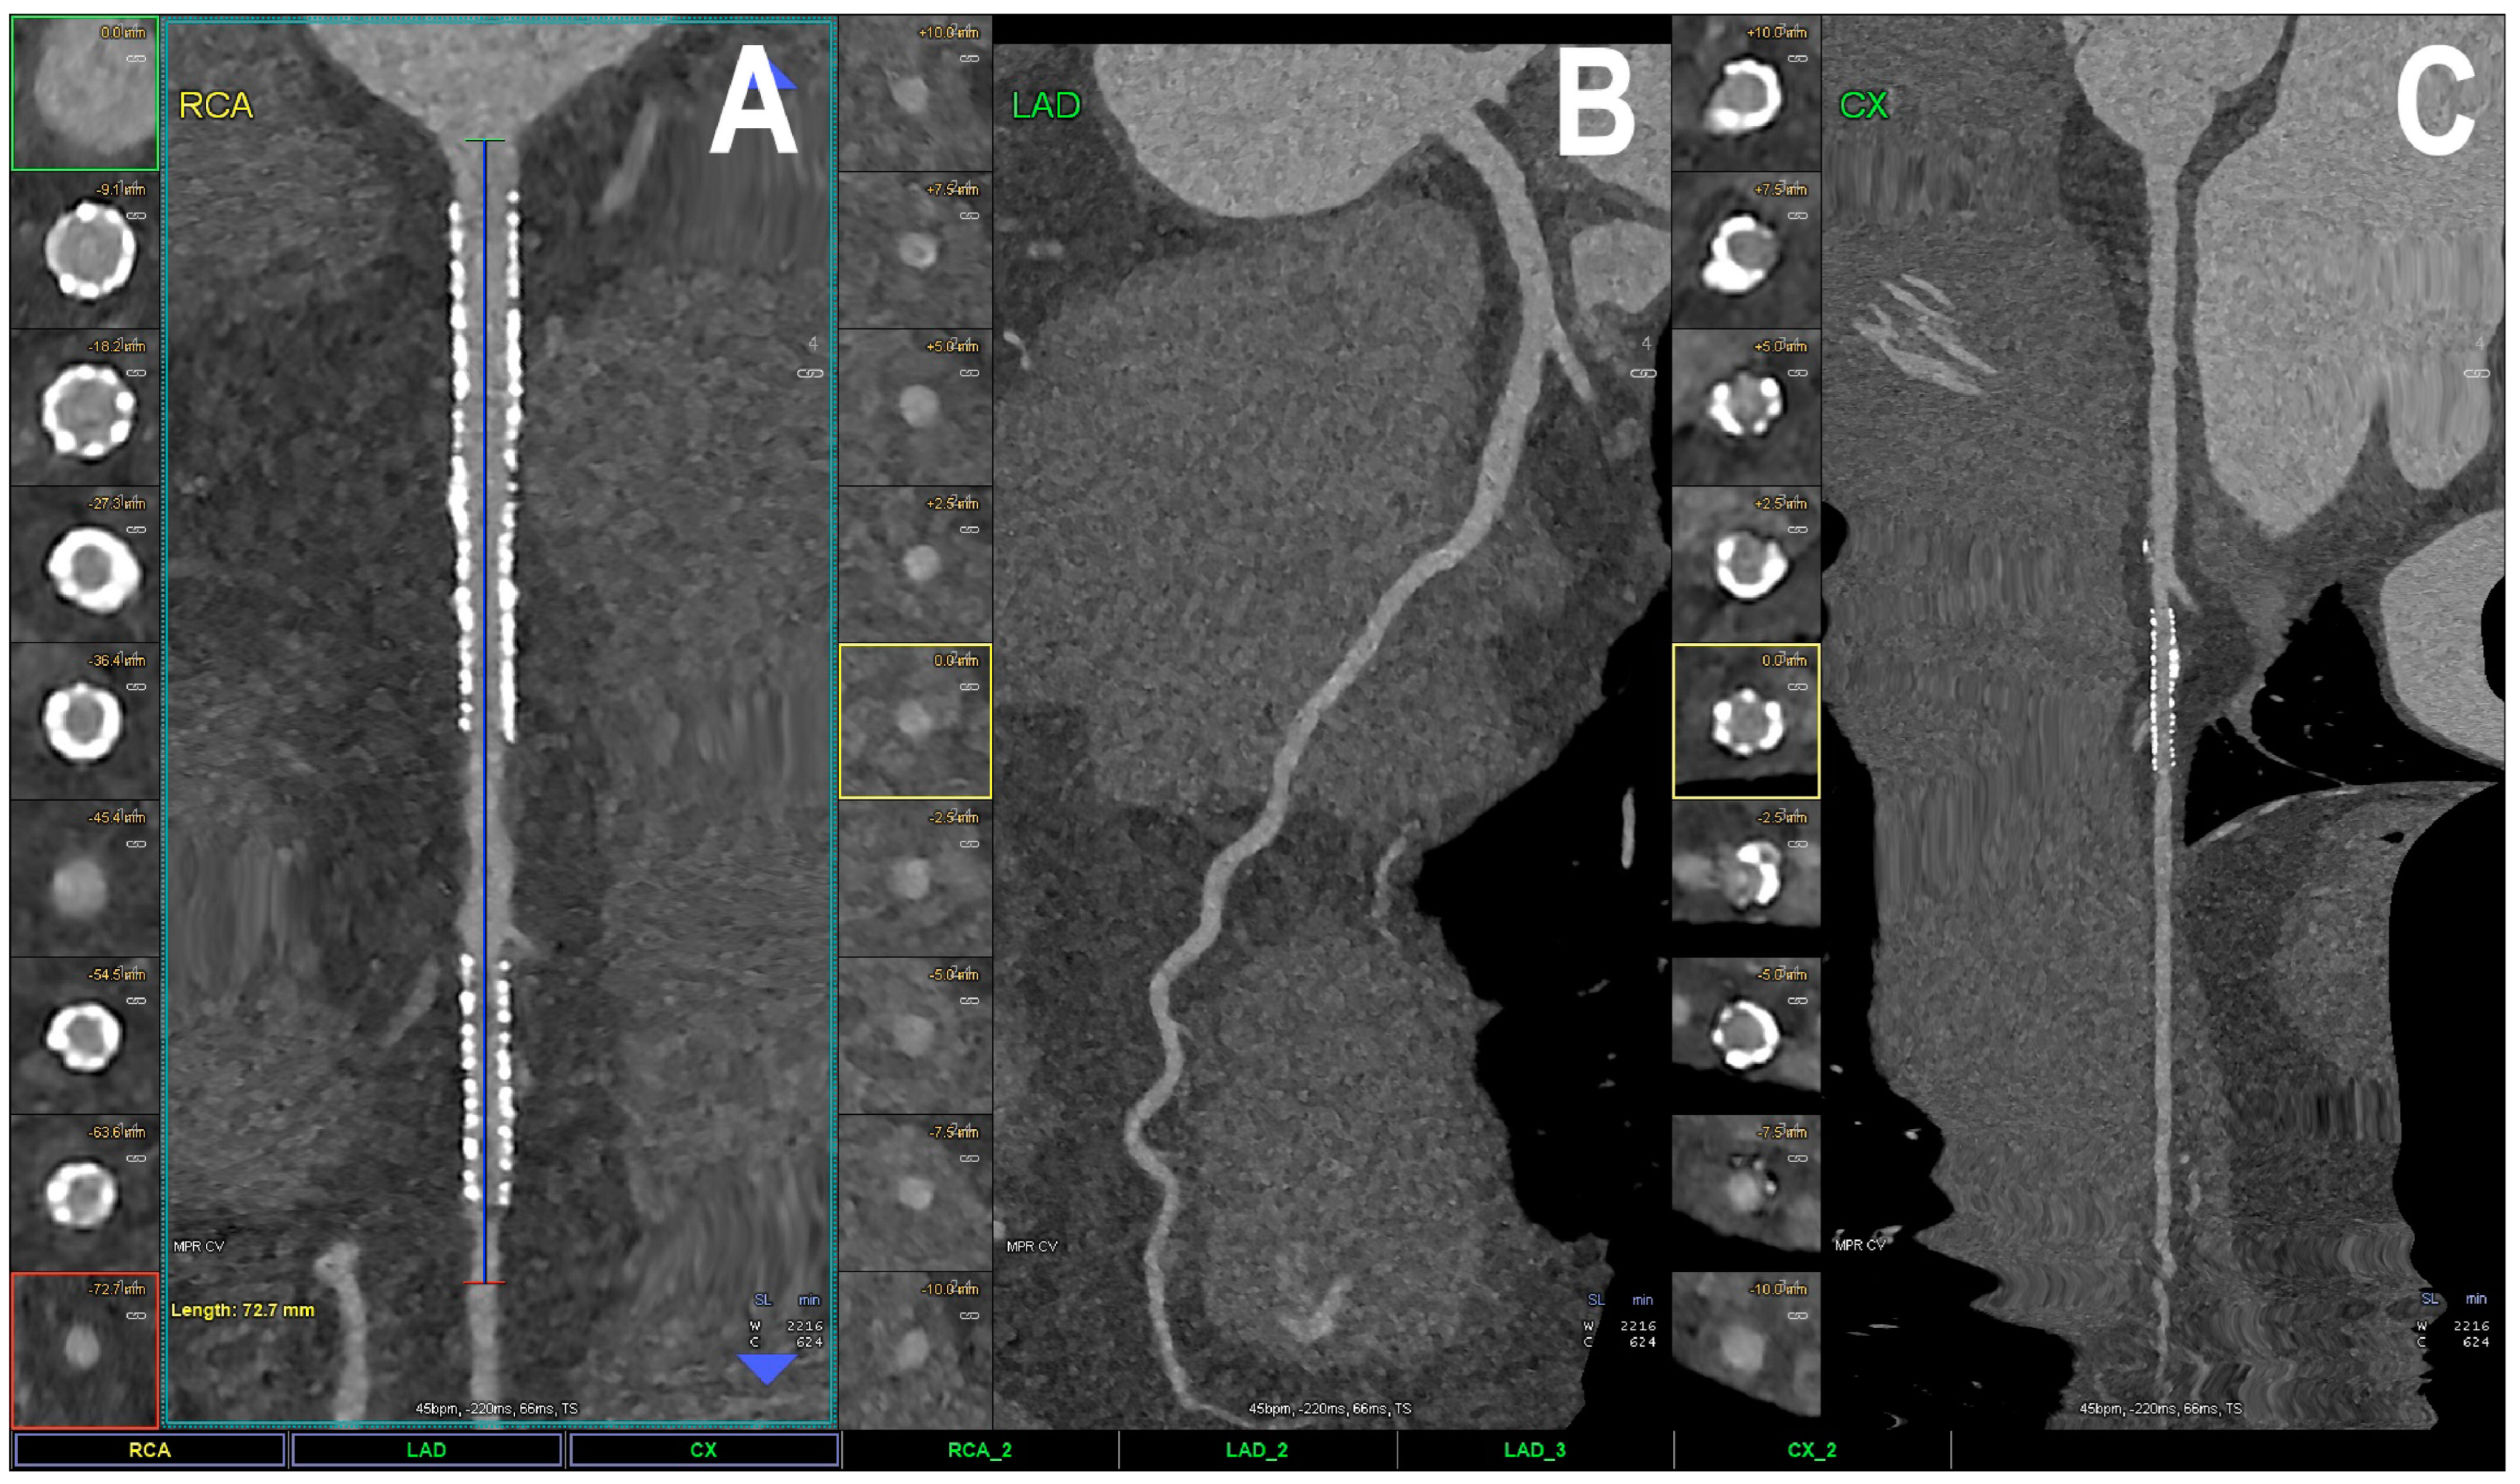

| Boccalini et al. [33] | 2022 | In vivo (human) | 8 | Coronary stent Dose reduction | Superior stent and lumen visibility with fewer blooming artifacts and lower dose radiation for PCCT versus conventional CT. |

| Mannil et al. [23] | 2018 | In vitro | Coronary stent | In comparison with EID-CT, PCCT offered superior in stent visibility, fewer blooming and partial volume artifacts, with a lower increase in the attenuation of the lumen inside the stent. | |

| Symons et al. [34] | 2018 | In vitro | Coronary stent | Better luminal depiction with lower image noise in PCCT compared to EID-CT. | |